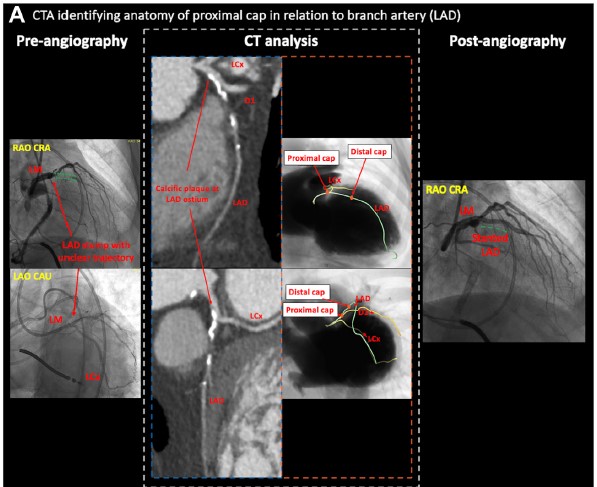

📢🔎Coronary #CTA solves ambiguity in #CTO #PCI. @PSandesara_MD @wjn_md present cases where #CCTA played an instrumental role. 💡 ➡️  https://t.co/ty0M3RHJz6

#JSCAI #CardiacCTA Special Issue 📚